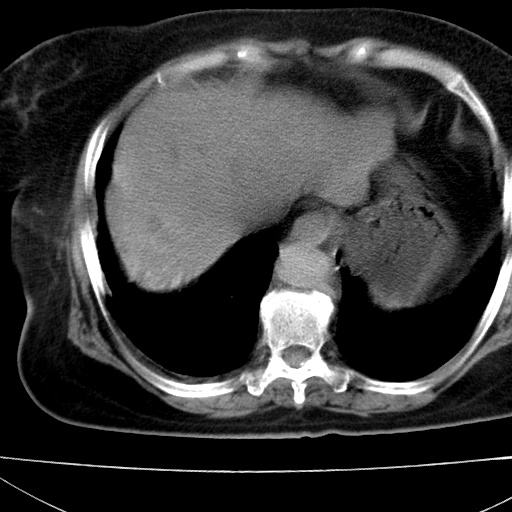

患者女74岁;右上腹胀痛1月,伴恶心,无发热;生活在疫水区。有术后病理及术后半年的追踪ct.

1)慢性血吸虫病(典型)。2)肝硬化。3)肝癌?4)胆囊炎。5)少量腹水。6)右侧少量胸腔积液。

肝脏体积缩小,肝裂增宽,边缘不平呈波浪状,肝右叶见分隔状条索形钙化,亦见多结节低密度灶,边界不清,肝周可见少许液性暗区,胆囊增大内密度均匀,脾脏下缘低于脏脏的下缘,胸腔亦见液性暗区,余未见明显异常.

诊断:1肝硬化并慢性吸血虫病,脾肿大

2肝内占位,考虑肝癌可能性大,建议做增强

3胆囊炎, 4少量腹水及胸水

胆囊增大饱满,壁增厚。胆囊颈部见软组织密度影。临近肝右叶前段见片状低密度区,病灶下部见条状钙化,少量胸腹腔积液。意见:胆囊颈癌累及肝脏。

病人以胆囊癌手术的,病理结果为中分化腺癌。

现在看看肝右叶内圆形低密度影你们考虑什么呢?

肝内圆形低密度影考虑扩张的胆管

请看3mm重建像如下: